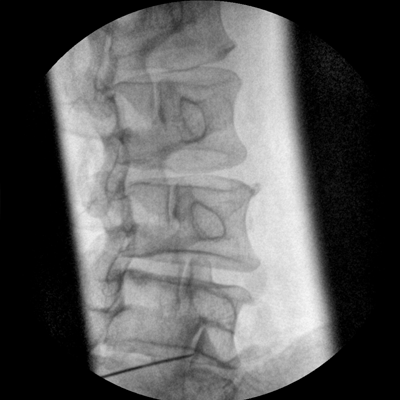

四維電動(dòng)運(yùn)動(dòng)控制,平滑定位,使得復(fù)雜角度快速實(shí)現(xiàn)。

專業(yè)的圖像處理系統(tǒng),為您提供高分辨率、高灰階圖像。